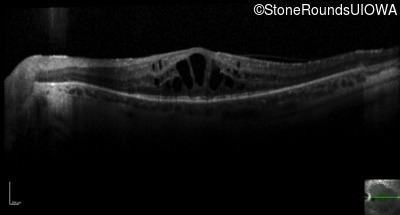

Optical Coherence Tomography - Right - 20/63 -1

Exemplar / OCT Stack

OCT Stack